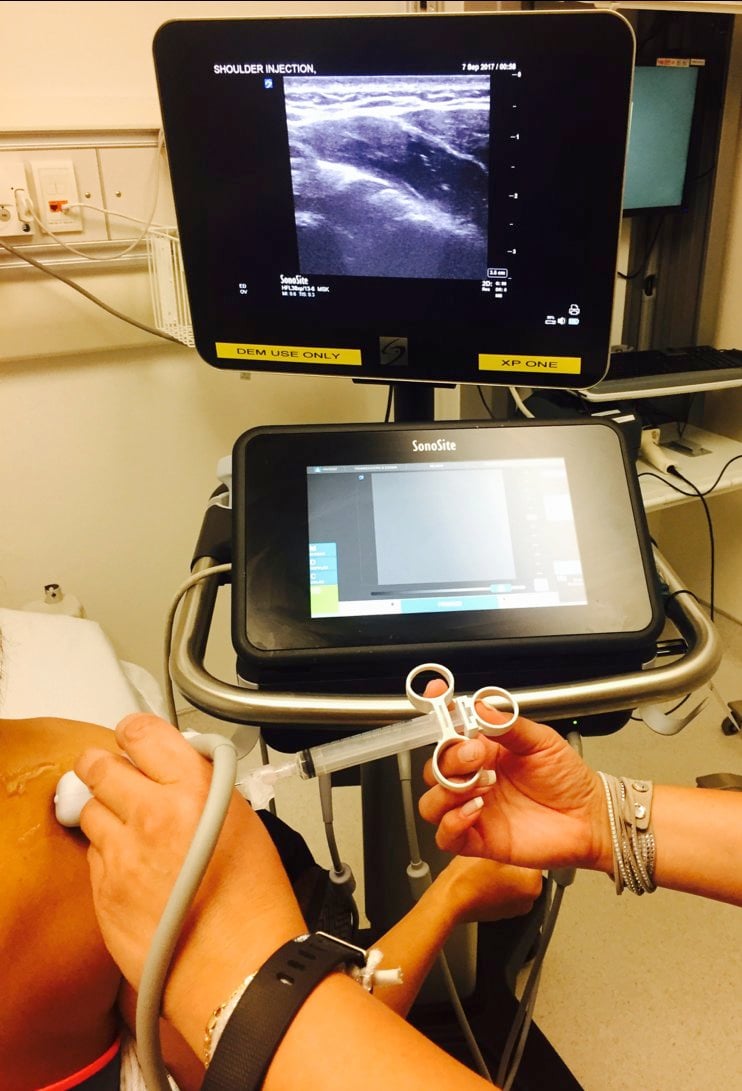

Place the ultrasound machine in front of the patient on the affected side.

Place a sterile cover over the ultrasound probe and apply sterile gel.

Place the probe in a transverse orientation over the infraspinatus and posterior glenohumeral joint, along the axis of the spine of the scapula and just caudal to the acromion.

Figure 2

Identify the humeral head, glenoid labrum, infraspinatus tendon, and joint capsule.